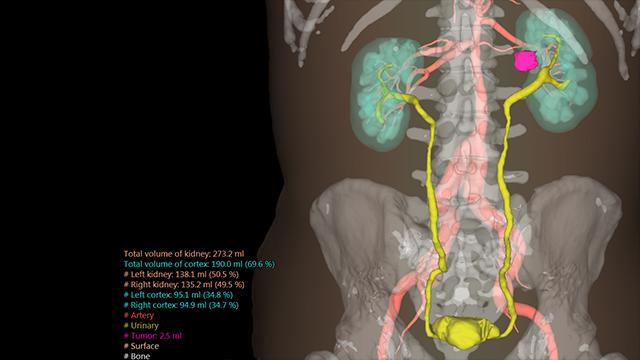

View X-Ray CT & MRI Scans Fast and Easily

FREE and easy to use 3D DICOM Viewer – for surgeons and patient education

Designed for surgeons, Pro Surgical 3D makes it easy to view patient scans quickly. Pro Surgical 3D facilitates the optimal 3D treatment and assessment workflows based on X-ray CT and MRI scans – and best of all, it’s FREE!

Everyone – including surgeons, patients and their loved ones – benefits from being better informed by the wealth of information buried within CT and MRI scans. Pro Surgical 3D gives surgeons more information to develop optimal treatment plans for patients. It also helps patients and their support group better understand their medical condition and proposed treatment options.

High-quality and fast 3D reconstruction and 3D rendering

Performs 3D reconstruction and volume rendering.